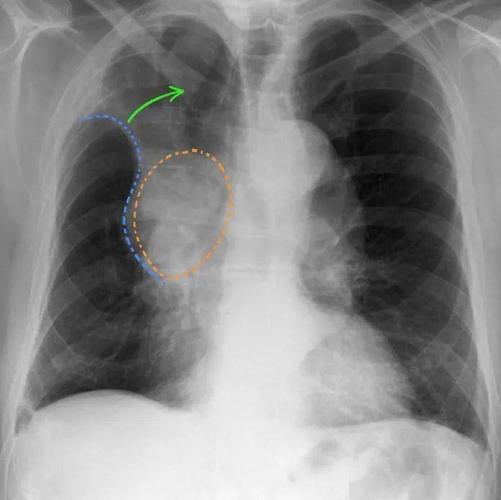

肺不张影像图片,肺不张影像

肺不张的影像学

肺不张:影像基本思路

肺不张影像表现

肺不张影像学表现

肺不张胸片表现

肺不张x线表现